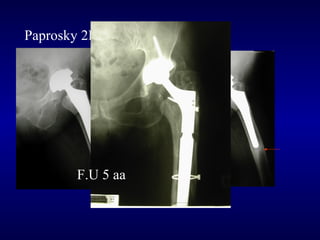

Paprosky 2B

F.U 5 aa